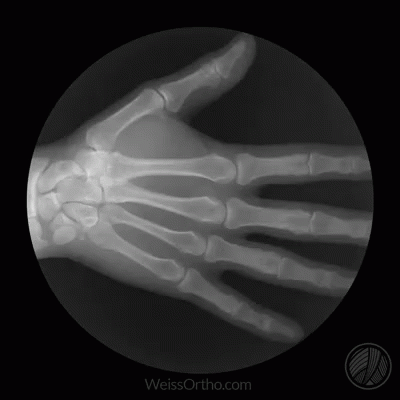

Trotz dieser Hinweise bleibt festzuhalten: Laborwerte allein reichen nicht aus, um Knochenkrebs sicher zu diagnostizieren oder auszuschließen. Sie dienen vielmehr als ergänzende Information zu klinischen Symptomen und bildgebenden Verfahren wie Röntgen, CT oder MRT. Die endgültige Diagnose wird durch eine Gewebeprobe (Biopsie) gestellt[2][4][5].